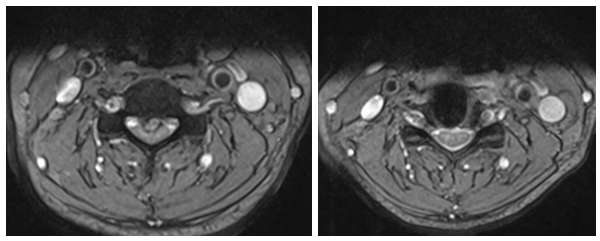

刘女士家属知道惠州市第三人民医院有个专治颈肩腰腿疼痛的科室,即来颈肩腰腿痛门诊就诊,入院后MRI示:颈3/4椎间盘变性并向后下脱出,颈3/4-6/7水平椎管狭窄及双侧神经根受压,以颈3/4水平狭窄为著。

术前MRI 和术后MRI

惠州市第三人民医院骨科医学中心主任武明鑫博士、颈肩腰腿痛科许球祥主任、孙进主治医师,详细询问刘女士病史、细致体格检查、仔细阅读辅助检查,经认真分析讨论,诊断为“脊髓型颈椎病”,认为刘女士病情目前并不适合继续保守治疗,建议行骨科中心阶梯疗法中的开放手治疗方案。